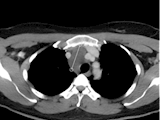

小小洞眼、大大学问——中南大学湘雅二医院桂林医院腔镜下切除复杂纵隔病变

近日,中南大学湘雅二医院桂林医院驻桂专家团队凭借多年来对复杂纵隔肿瘤的诊断和手术经验,为患者成功切除一例巨大复杂纵隔病变。今年40岁的秦老师在中南大学湘雅二医院桂林医院开展的每年例行的常规体检,检查发现其胸部主动脉旁存在一个巨大占位病变,这一检查结果可吓坏了秦...